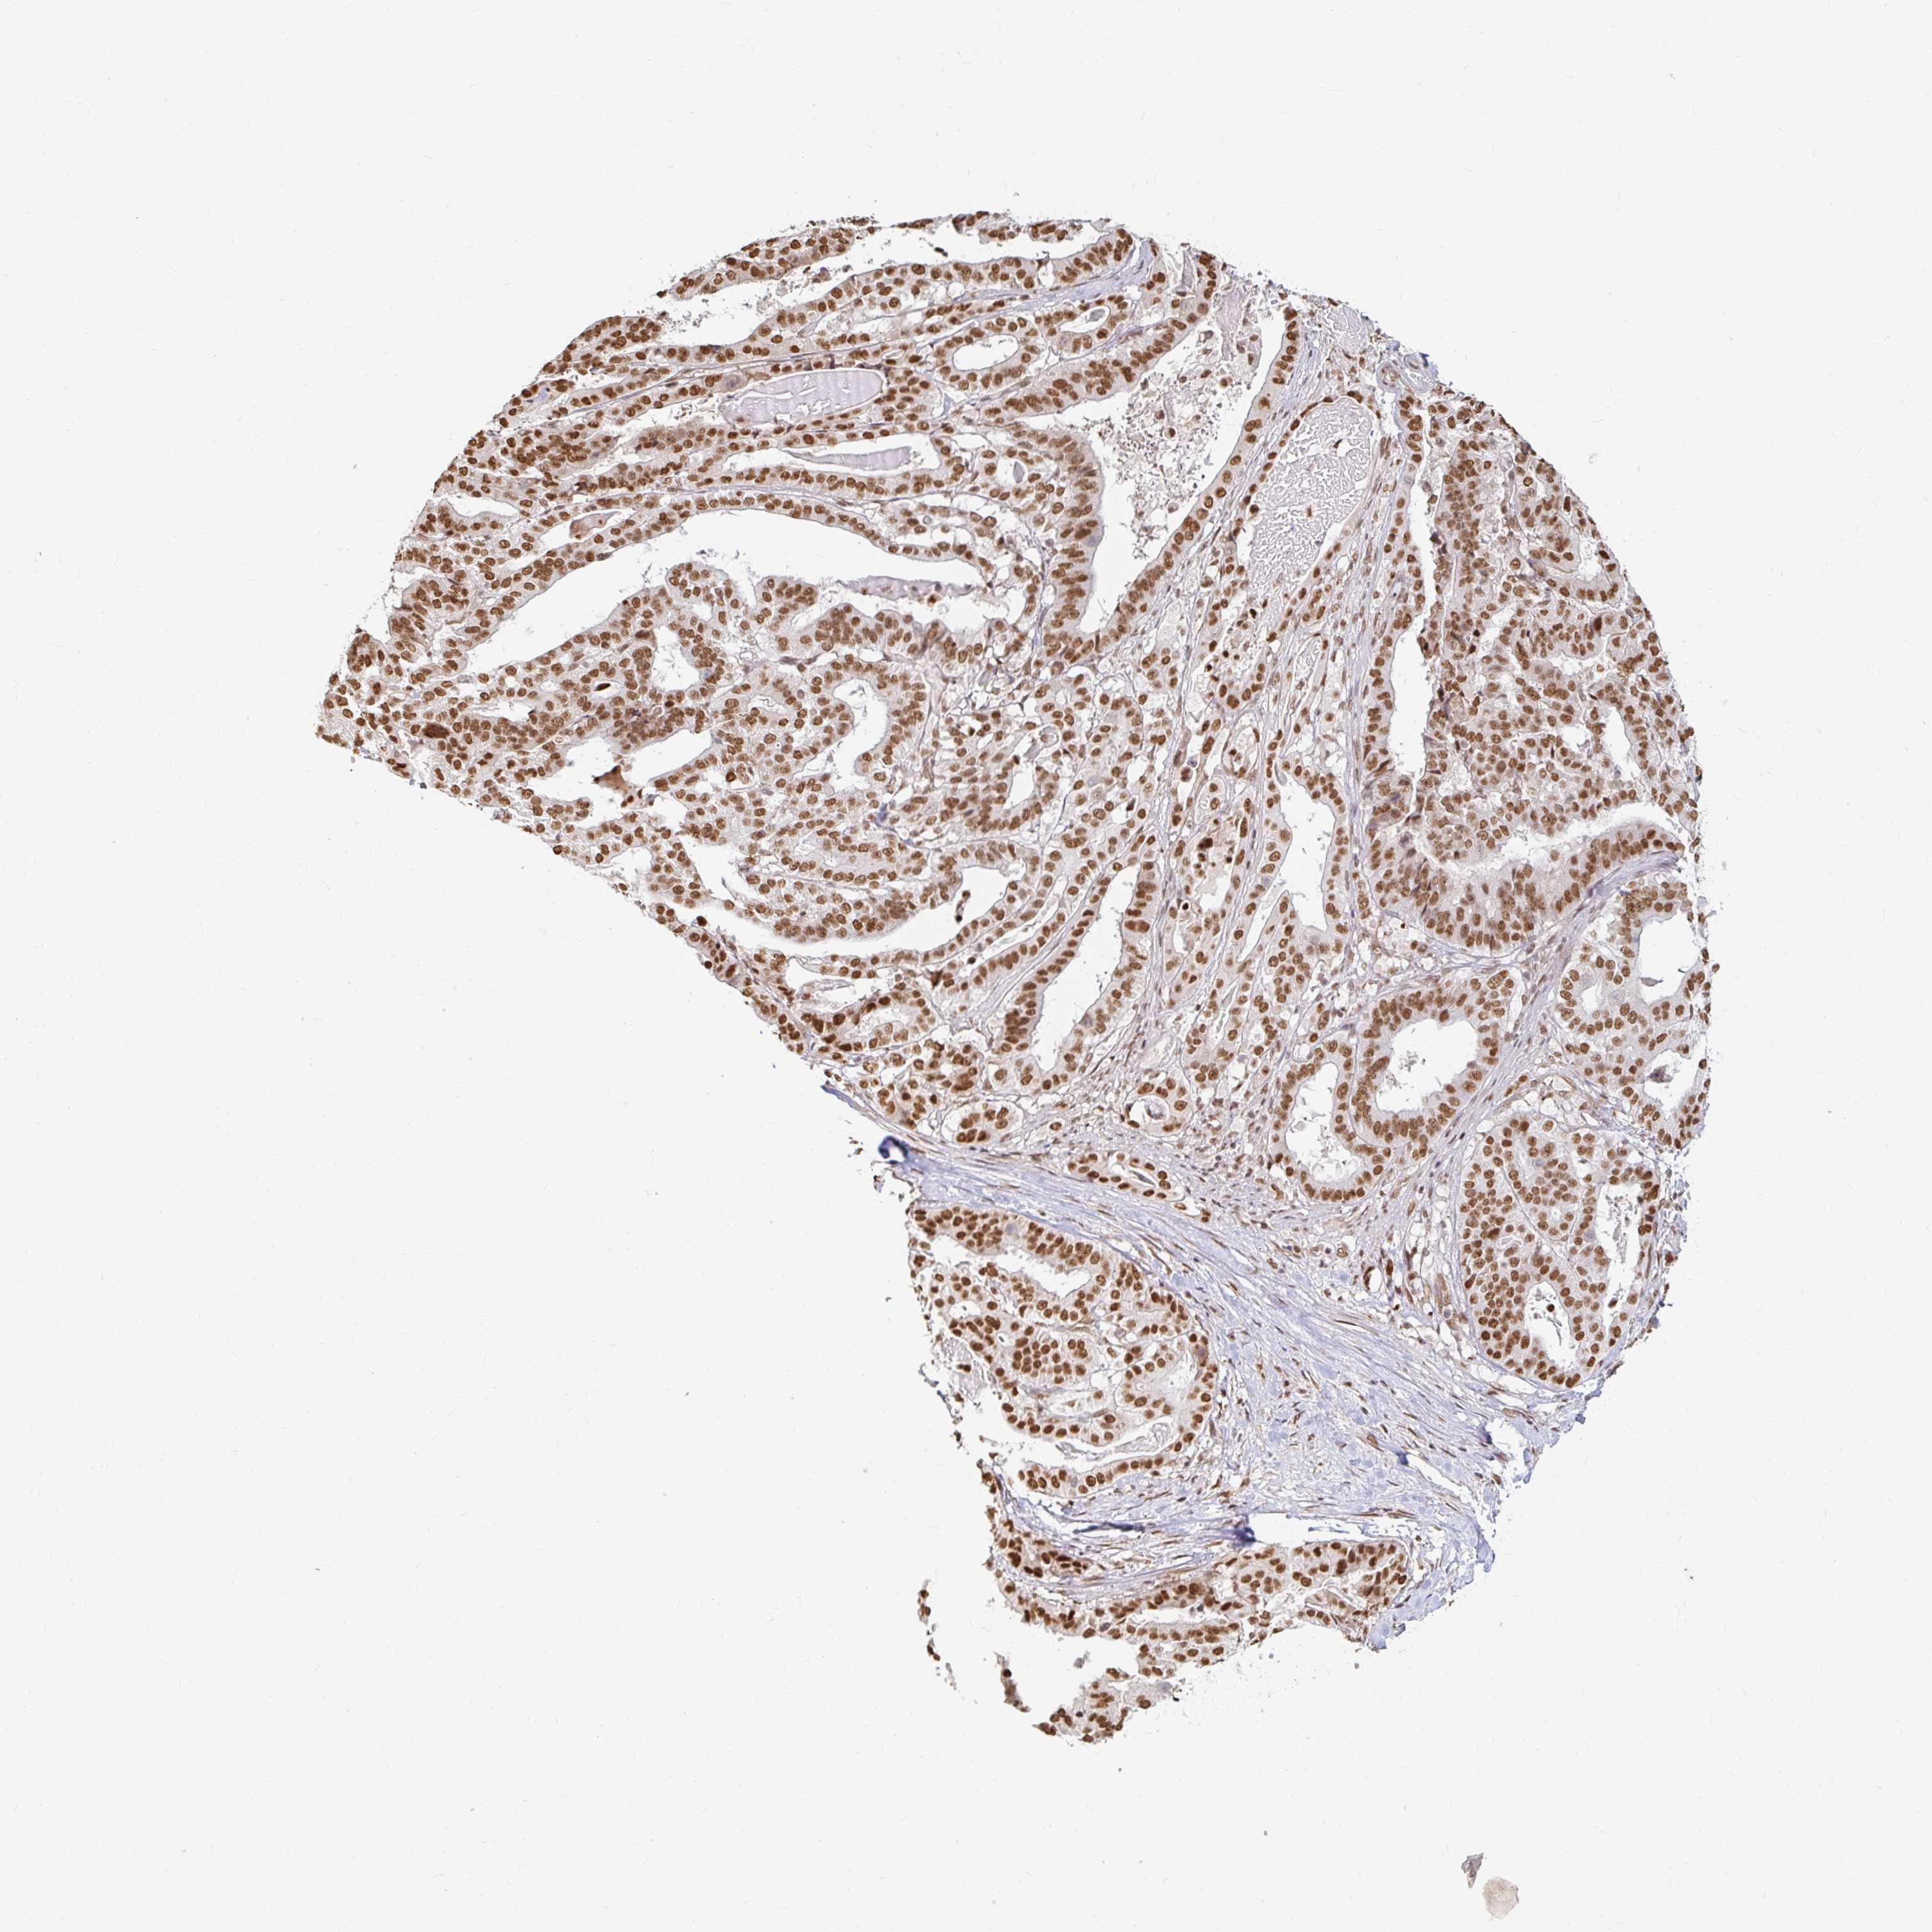

STOMACH CANCER - Protein expressioni

A mouse-over function shows sample information and annotation data. Click on an image to view it in a full screen mode. Samples can be filtered based on level of antibody staining by selecting one or several of the following categories: high, medium, low and not detected. The assay and annotation is described here.

Note that samples used for immunohistochemistry by the Human Protein Atlas do not correspond to samples in the TCGA dataset.

Antibody stainingi

Antibody staining in the annotated cell types in the current human tissue is reported as not detected, low, medium, or high, based on conventional immunohistochemistry profiling in selected tissues. This score is based on the combination of the staining intensity and fraction of stained cells.

Each image is clickable and will lead to virtual microscopy that enables deeper exploration of all samples and also displays staining intensity scores, fraction scores and subcellular localization as well as patient and tissue information for each sample.

Antibody HPA041057

Antibody HPA058707

Antibody CAB011532

Staining

High

Medium

Low

Not detected

Intensity

Strong

Moderate

Weak

Negative

Quantity

>75%

75%-25%

<25%

None

Location

Nuclear

Cytoplasmic/membranous

Cytoplasmic/membranous,nuclear

Adenocarcinoma, NOS

Adenocarcinoma, High grade